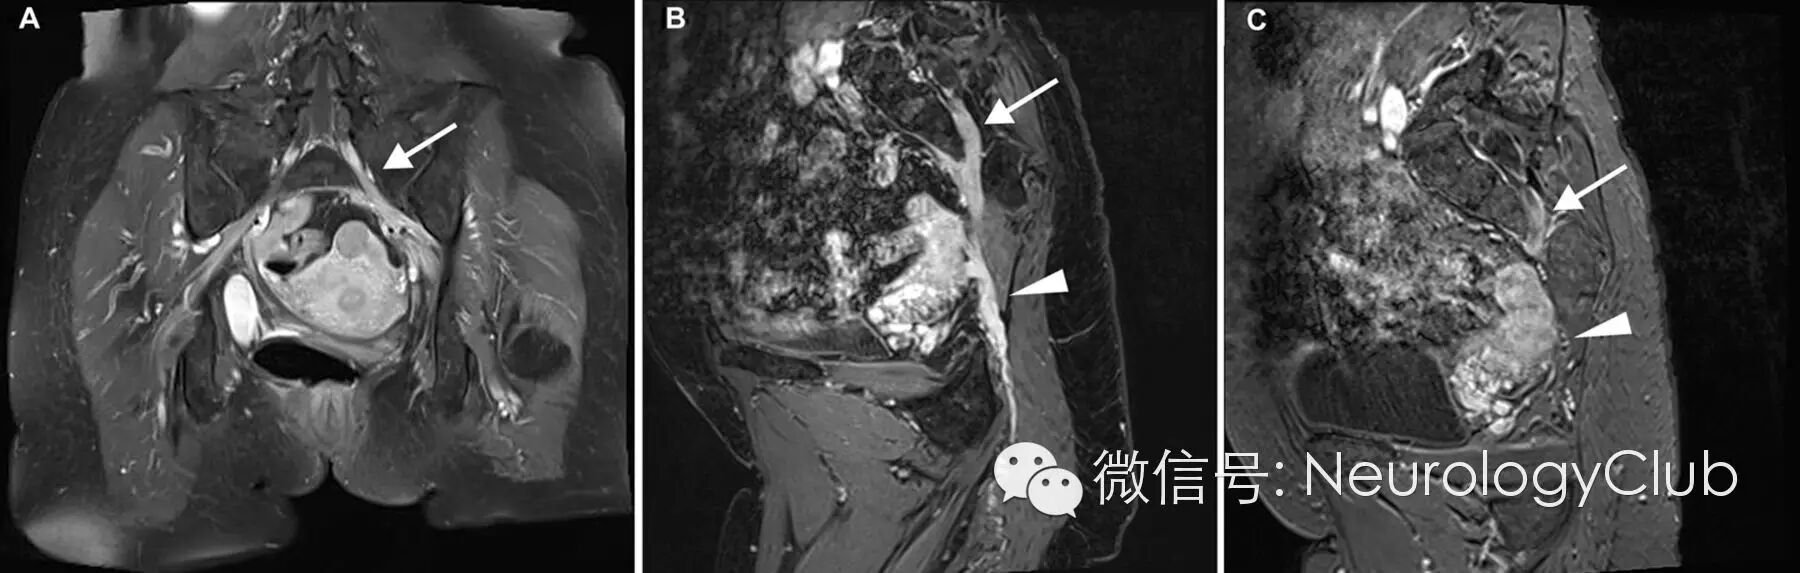

盆腔MRI提示左侧腰骶神经根、丛和坐骨神经异常增粗强化信号(图1 A,B);头颅MRI提示左侧三叉神经强化信号(图2 A);全身PET检查提示双侧臂丛,左侧腰骶神经根和坐骨神经代谢增加。

(图1:冠状位T1增强压脂像[A]和斜矢状位容积内插摒气检查T1压脂像[B]示左侧S1神经根[箭]和左侧坐骨神经[箭头]异常增粗与强化;化疗后,可见病灶缓解[C])

重复脑脊液细胞学检查证实为大B细胞淋巴瘤。骨髓检查无血液系统恶性肿瘤证据。患者入院后神经系统症状持续进展,出现右腿无力并觉双侧面颊麻木。患者接受R-HDMTX(甲氨蝶呤、倍他米松、甲酰四氢叶酸和立妥昔单抗)系统性化疗方案并三联鞘内疗法(甲氨蝶呤,阿糖胞苷和琥珀酸钠氢化可的松)。治疗后,患者神经系统缺失症状逐渐改善,随访MRI和PET异常病灶同时缓解(图1C,2B和3B)。